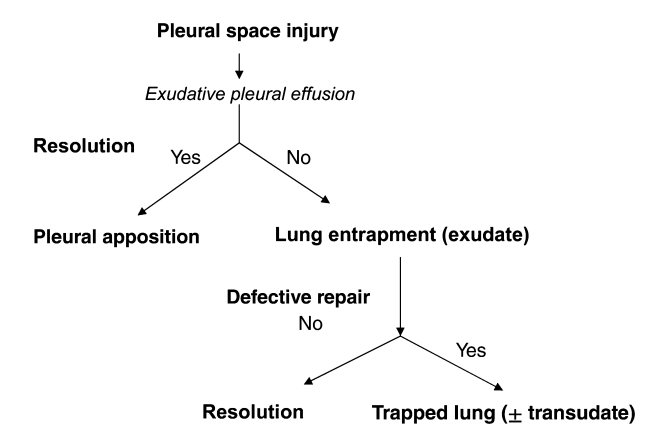

4/Lung entrapment is when the lung cannot fully expand due to an active disease that restricts the expansion of the lung and/or visceral pleura. This is typically associated with an exudative effusion. @tony_breu @KevinSwiatek

5/ Trapped lung is when the lung cannot expand due to a remote inflammatory condition that leaves a collagenous or fibrinous peel on the viscera pleura that prevents lung expansion. The pleural fluid can be transudative or exudative. @scall1200 @cderekleiner @rva_IntMedPD

6/Let’s dive into lung entrapment. The most common cause of lung entrapment is due to pleural malignancy with an estimated 30% of malignant effusions leading to lung entrapment. However, pleural infections or inflammation can also lead to lung entrapment.

8/ Lung entrapment secondary to an infectious process is typically due to an increase in the elastic recoil of the atelectatic/consolidated lung with an increase in pleural fluid production from the visceral pleura.

11/ The overarching goal of treatment for lung entrapment is to treat the underlying cause, i.e. infection, inflammation, or malignancy as most lung entrapment will resolve with treatment.

12/In trapped lung, the fibrotic process affecting the visceral pleura causes an increase in the negative pleural pressure resulting in fluid accumulation and reduction in the removal of fluid by pleural lymphatics. @UpToDate @gsmartinmd @jackpenner